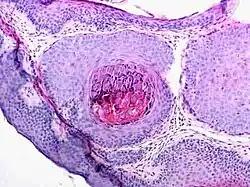

Histologie des Molluscum contagiosum

Dank des charakteristischen Aussehens ist meist eine Blickdiagnose möglich. In Zweifelsfällen kann eine histopathologische Untersuchung die Diagnose sichern.